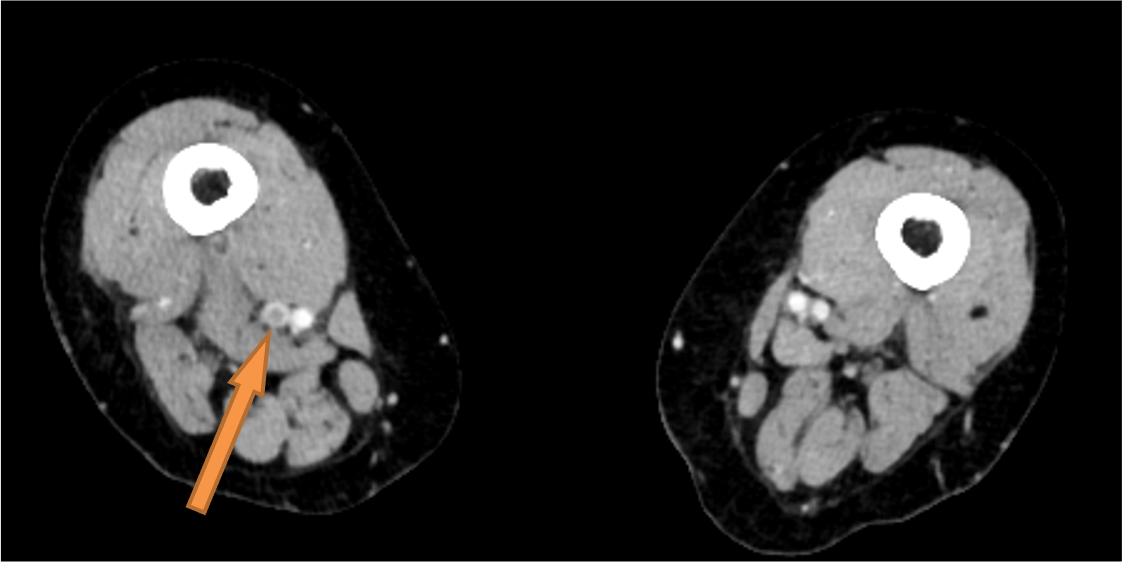

深部静脈血栓症(Deep Vein Thrombosis:DVT)と肺血栓塞栓症(Pulmonary Embolism:PE)は静脈血栓塞栓症(Venous Thromboembolism:VTE)として一つの連続した病態として捉えられる。致死的PEの剖検検討において塞栓源の70-90%以上が下肢静脈内血栓であると報告されている(1,2。肺血栓塞栓症および深部静脈血栓症の診断、治療、予防に関するガイドライン(2017年改訂版)においても、CTは静脈造影、下肢静脈超音波検査と同様にClass I に分類されている。超音波検査のように術者のテクニックに左右されず安定した情報が得られる点でCTは優位であるが、コントラストの不足は常につきまとう問題である。造影CTにおいて動脈と異なり静脈は十分なコントラストが得られにくい。特に下肢静脈ではそれが顕著で、症例によっては造影効果がほとんど得られない場合もあり、診断に苦慮することも少なくない。Photon Counting CTは検出器の素材や構造、カウンティングメカニズムによって従来CTよりもコントラストの改善、高分解能、ノイズ低減、低被ばく撮影が可能となっており、DVT検索において有利と考えられる。

その後、総量600mgI/kgに到達するまで造影剤を追加注入し、240秒後に横隔膜から下肢までを撮影している。下肢静脈はコントラストが得られにくいため60keVの仮想単色X線画像を基本として作成している。60keV画像では100kVp撮影よりもヨード値の向上が得られ、より正確な診断に寄与すると考えている。